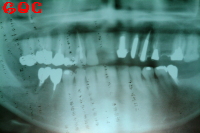

▼初診時レントゲン![]() |